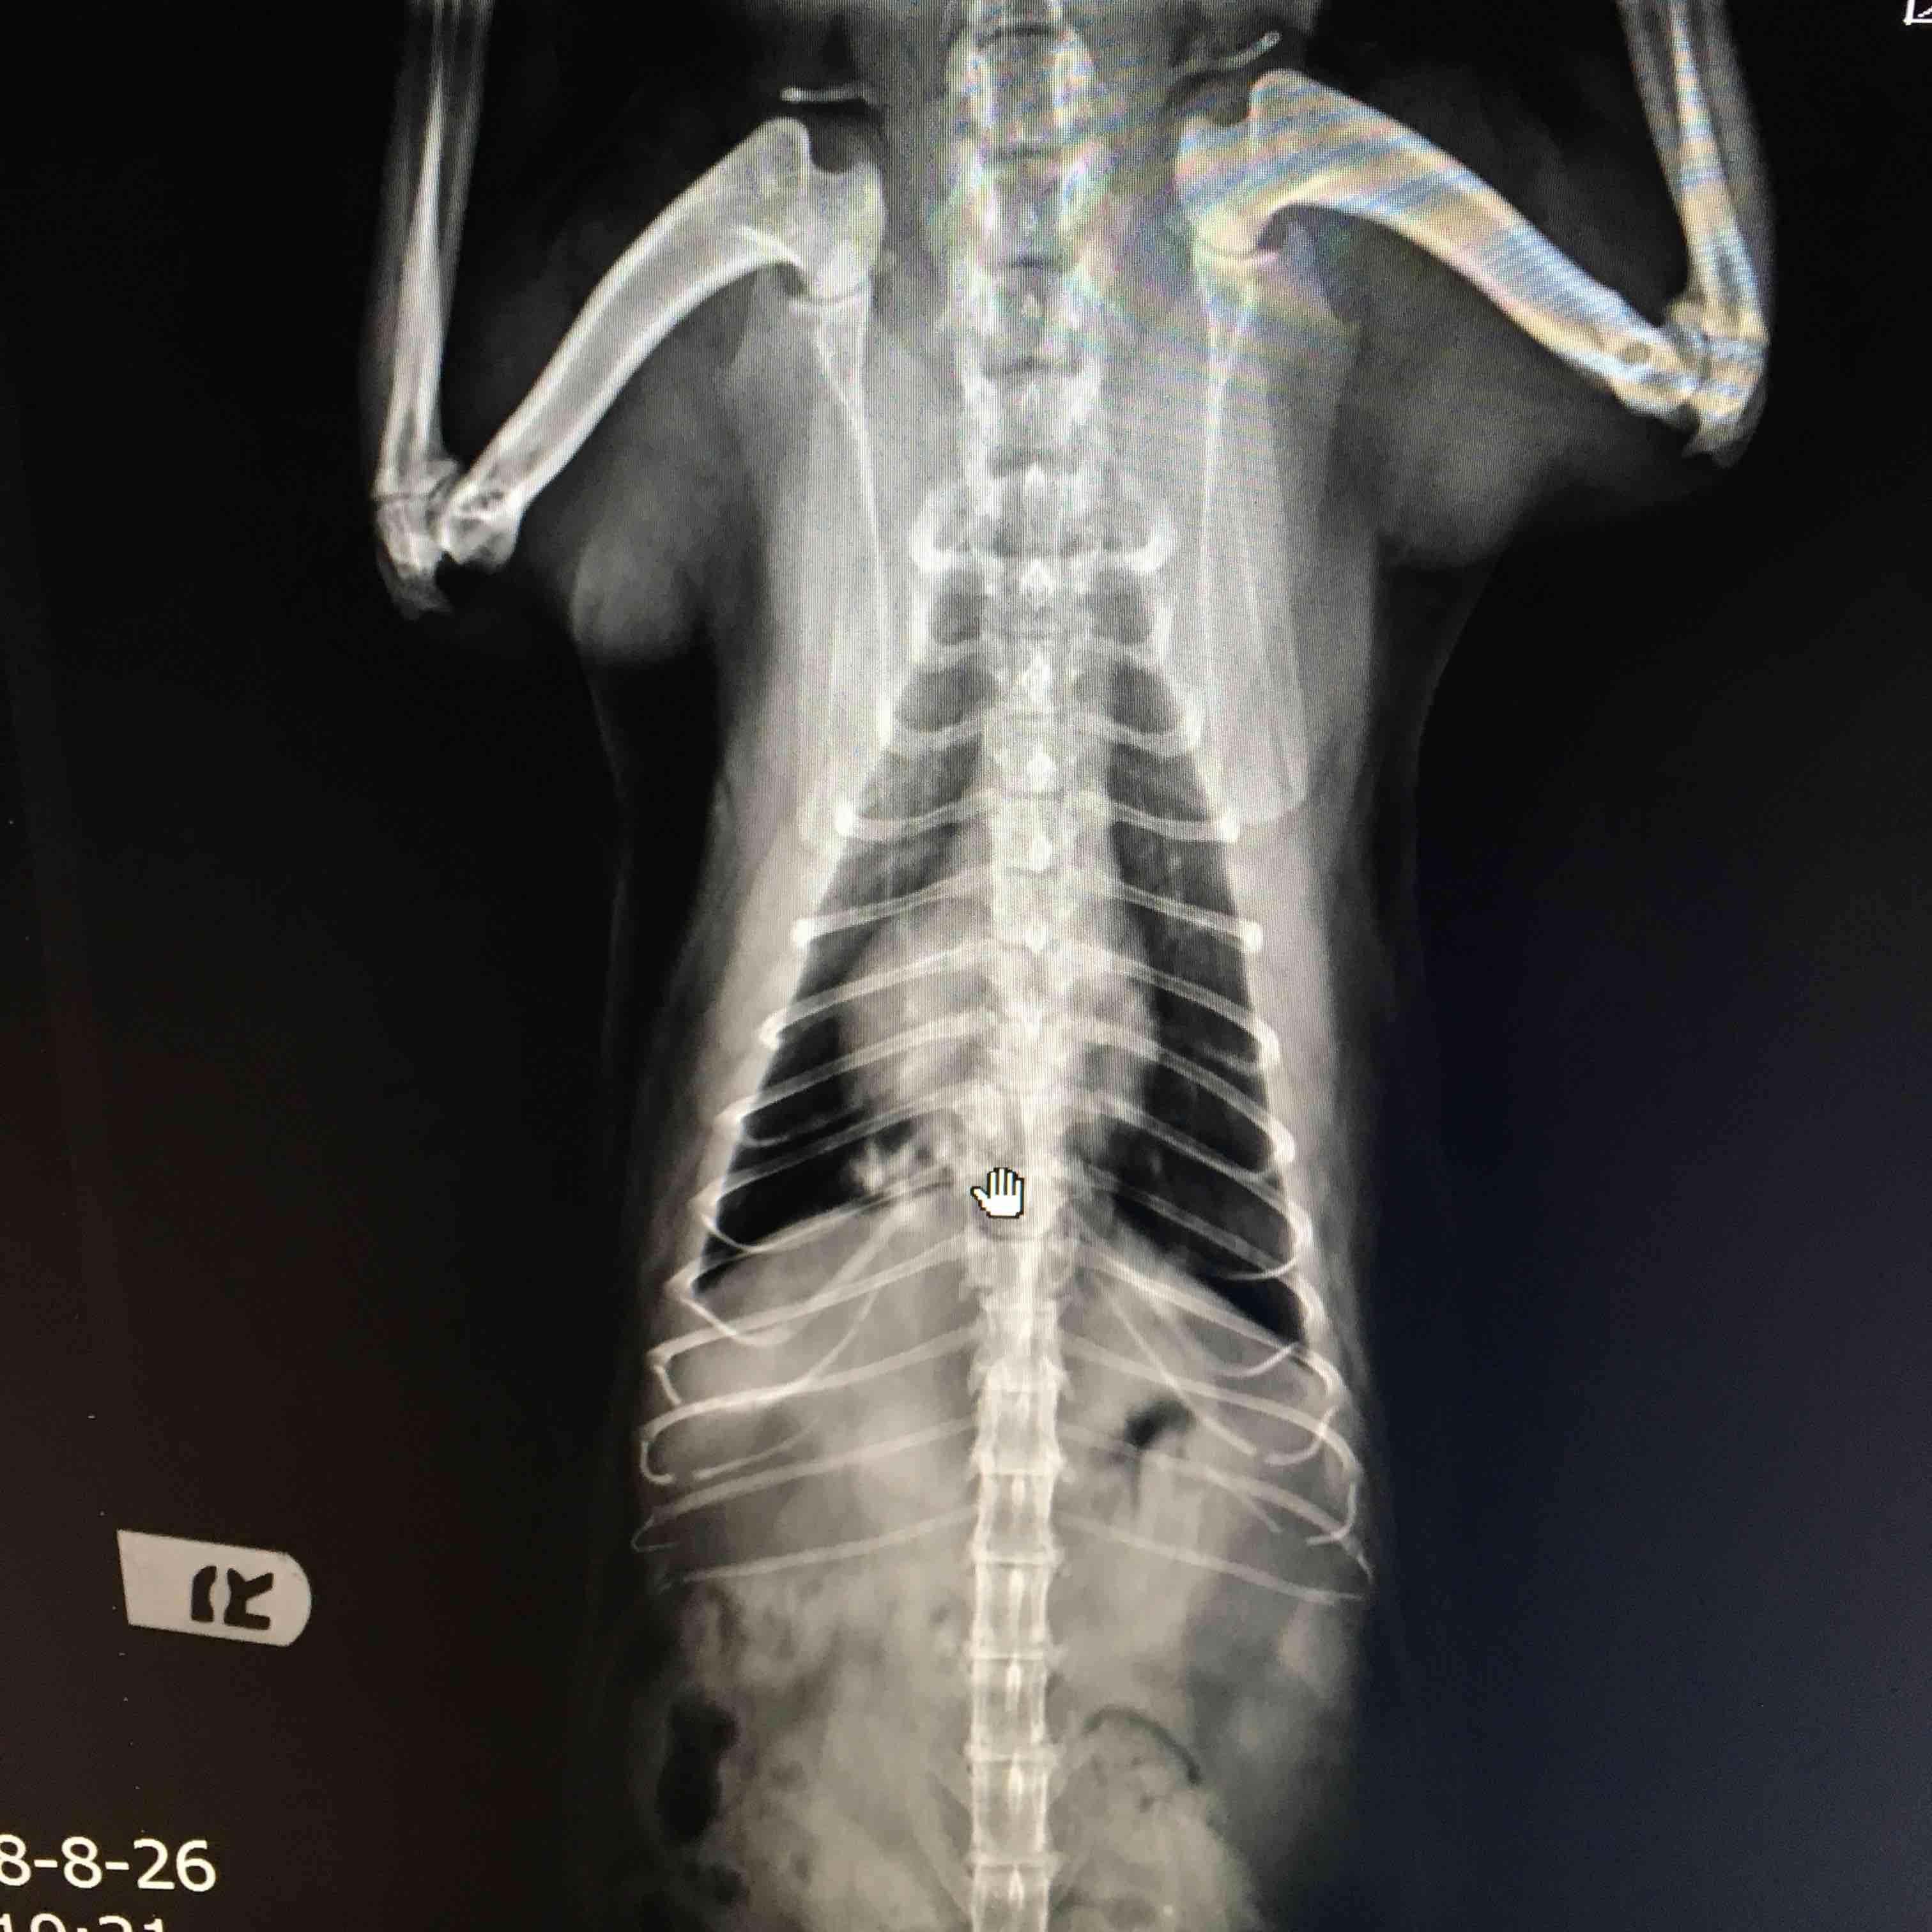

Coughed for a weekend in May. After Xra​y, was suspected of lung cancer. Since he has HCM so CT or surgery will be too risky. We took a palliative treatment option and he was subscribed with steroid and medication for HCM. When first detected, respirations aprox.​ 28/min. three months later, now accelerated to 40+/min, monthly Xray showed signs of spreading. Apart from it, he's as if not sick at all, sweet and happy. I wonder if there's more I can do to help him live longer with life quality.